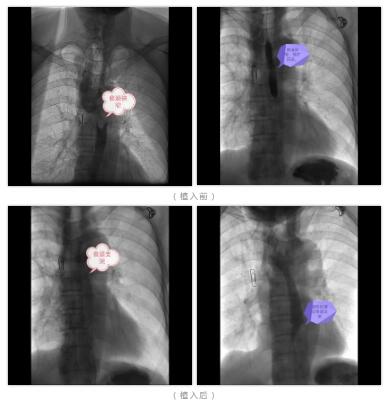

近日,我院肿瘤科联合介入导管室成功为一位食管癌出现吞咽困难并发症的患者行DSA引导下行食道支架植入术。这是我院首例DSA下行食道支架植入术。DSA引导下食管支架植入术的开展,为不少食管癌晚期、食管狭窄、食管瘘患者重新打开了狭窄的通道,解决了患者进食问题,为后续的治疗和康复提供了保障。

在介入导管室团队的密切配合下,郭添胜主任精准地在患者食管狭窄段放置了支架,顺利将狭窄段的食管管腔扩张。术后次日,患者已经可以正常进食,现病情好转,正在进行后期的康复治疗。

食管支架植入可在内窥镜直视下或X线透视引导下或内窥镜联合X线透视引导下操作。使用X线引导放置的优点是可以实时显示导丝的位置,准确判断导丝是否通过病变段进入胃内,动态监控支架释放过程及支架膨胀情况,以及时调整支架位置,定位更准确,操作既简单又快捷。